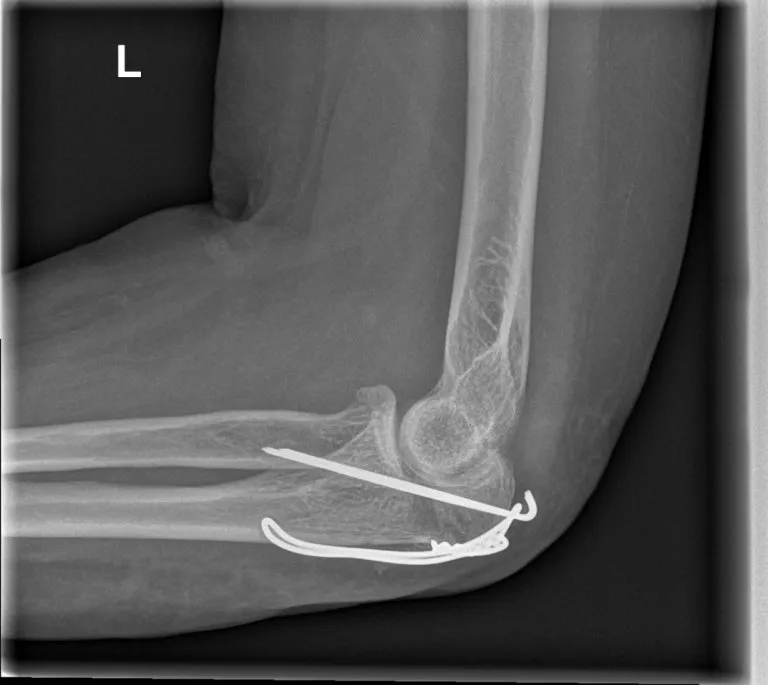

- Ingreep: De chirurg brengt onder verdoving de botfragmenten van de olecranonfractuur weer op de juiste plaats. Vervolgens worden ze vastgezet met metalen materiaal. Vaak gebruikt men een combinatie van pinnen en een staaldraad (tension-band cerclage techniek) om het afgebroken stukje ellepijp stevig vast te zetten. Als de breuk in meerdere stukken is, kan de arts ook kiezen voor een plaat en schroeven om alles te fixeren.

- Verwijderen van materiaal: Omdat het metalen fixatiemateriaal vlak onder de huid zit bij de elleboog, kan dit na verloop van tijd irritatie geven. Als u last heeft van het uitstekende materiaal, kan de chirurg het verwijderen zodra de breuk volledig genezen is (meestal na 6 tot 12 maanden). Dit is geen verplichte ingreep; als het geen hinder geeft mag het materiaal blijven zitten.